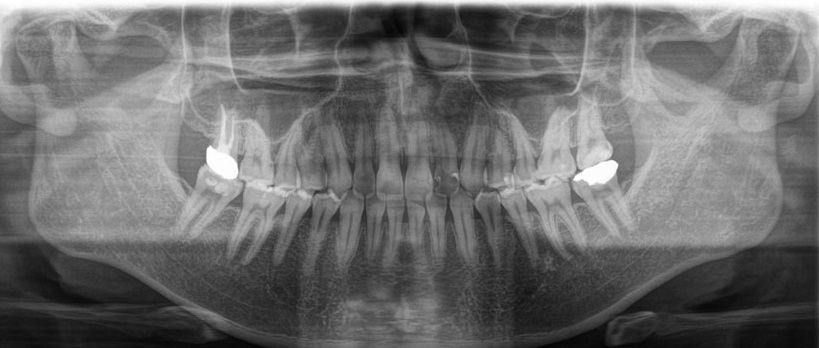

「CT」を活用することで、三次元での撮影が可能になります。通常のレントゲンは二次元のため、詳細な骨の厚さや血管・神経の位置などまでは確認することができません。しかし、CTはこれらを撮影できます。

歯科治療において、「見える/見えない」は治療結果に大きく影響するため、CTを活用することで、治療精度向上に努めています。

肉眼では見えない虫歯や歯周病の進行度を確認します。また、歯を支える顎の骨の状態もチェックします。